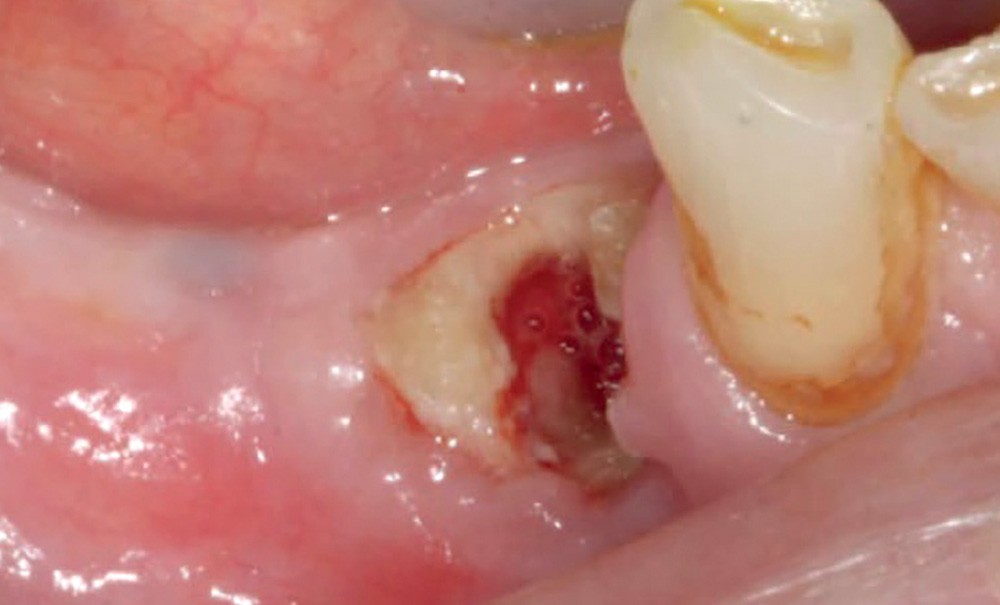

La définition de l’ONM doit permettre de bien faire le diagnostic et d’écarter toutes les autres causes d’ostéite possibles.

L’American Association of Oral and Maxillo-facial Surgeons (AAOMS) a proposé en 2014 une actualisation des critères caractérisant l’ONMB (ONM liée aux bisphosphonates) [2].

Elle est définie selon quatre critères :

– traitement par antirésorbeurs osseux, en cours ou antérieur (bisphosphonate, dénosumab, AA, etc.) ;

– exposition osseuse durant plus de 8 semaines ;

– absence d’antécédent de radiothérapie dans la région maxillaire ;

– absence de localisation métastatique au niveau des maxillaires.

L’ostéite peut revêtir différentes formes, en fonction de son évolution :

– stade 0 : aucun signe clinique apparent de nécrose…